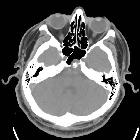

CT

CT is generally not sensitive for such lesions, mainly because of posterior fossa artifacts and the near CSF density of the mass. The bony clival defect is, however, visible as a well-demarcated smoothly corticated region, without aggressive features.

Occasionally an osseous stalk is seen at the base of the lesion which is said to be pathognomonic in this context .